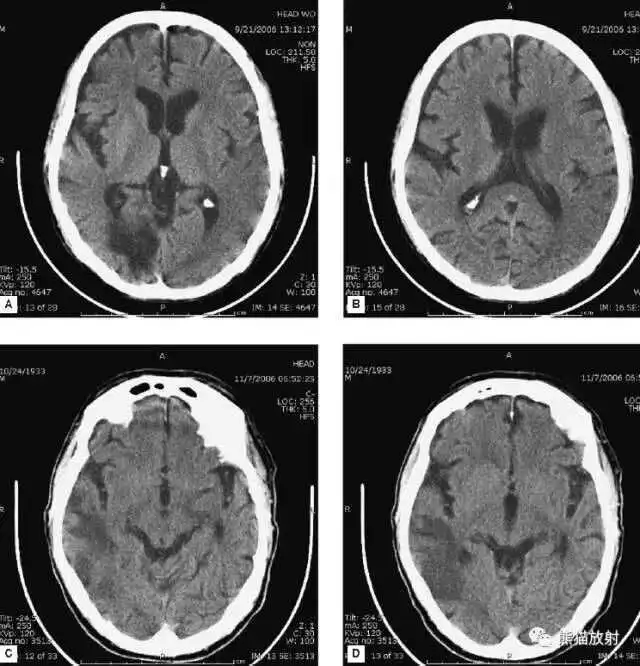

A:四脑室积血;

B:中脑导水管、环池、右侧侧脑室颞角积血,前交通动脉处(动脉瘤好发位置)出血密度较高;

C:三脑室积血;

D-F:侧脑室积血,蛛网膜下腔出血(血液代替了脑脊液)。